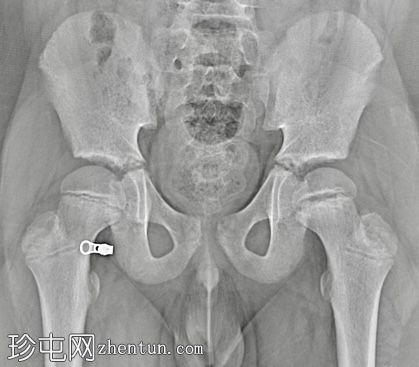

X线片

左侧股骨骨骺增宽且不规则。

左侧股骨近端骨骺板增宽,伴有股骨近端骨骺向后内侧滑脱。影像学表现符合左侧股骨头骨骺滑脱。

急诊X线片显示可能存在股骨骨骺骨折,因此需要入院并进行皮肤牵引。入院后,CT扫描证实为左侧股骨股骨头骨骺滑脱。手术固定安排在次日进行。

诊断主要依靠影像学检查,通常采用髋关节正位和蛙式侧位片。治疗方法一般包括原位经皮克氏针固定,以防止进一步滑脱,从而降低股骨头坏死和软骨溶解的风险。